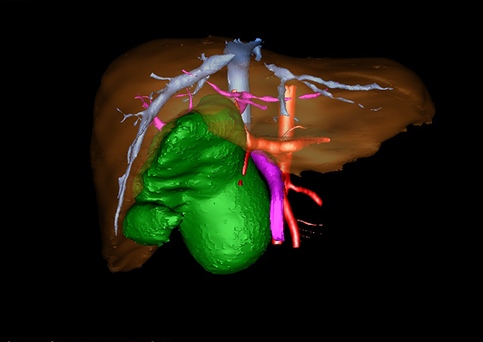

10、三维重建虚拟肝脏、胆道显像技术

三维虚拟肝脏技术是在二维影像学资料如CT等图像的基础上,通过三维重组软件和工具,比如青岛大学附属医院与海信医疗集团联合自主研发的海信计算机辅助手术系统(Hisense Computer Assisted Surgery,Hisense CAS),目前已投入临床并指导实际应用,利用该类系统对二维影像学的数据资料进行三维立体分析,重组形成立体的、有空间结构的、虚拟的肝脏三维图像。这项技术较传统的二维平面成像技术,有着明显的优势,3D虚拟肝脏技术可以构造出一个虚拟的、可视化的肝脏模型。通过对这种模型的观察,可以很容易地分辨出肝脏器官的组织结构、解剖特点,直观研究肝外胆总管的形态差异,明确肝内胆管的形态、走形、是否合并扩张、狭窄及结石,胰胆管合流的形态及共同通道内是否有狭窄、扩张和结石等病变情况,预先规划处理可能合并存在的肝内胆管扩张、狭窄或其他复杂胆道畸形,清晰地显示肝内脉管系统,包括门静脉、肝动脉及肝静脉的走行、分支,并可多角度、全方位观察病变胆道与其周围重要血管尤其是伴行的门静脉之间的解剖关系,大大提高了外科医师在术前对肝脏内部各管道结构及其变异判断的精确性和可靠性,精准地对病变进行判断和评估,还可根据患者自身的病变特点,制定出合理、个体化的手术方案,最大限度地降低术中和术后并发症发生率,并术中导航实时指导手术,提高手术的精准性和成功率。

图10:先天性胆管扩张症囊肿型三维重建虚拟肝脏、胆道显像

a 图为术前二维CT扫描图像,箭头所示为肝内胆管扩张;b 图为CT经多平面重组技术(MPR)图像后处理所得的重建图像,可显示胆总管明显扩张合并肝内胆管扩张;c 图为MRCP显示胆总管呈囊柱状扩张,直径>1 0 cm,伴肝内胆管扩张;d 图示Hisense CAS三维重建清晰显示肝脏、胆道系统及其与门静脉、肝动脉、肝静脉等之间的空间解剖关系;e 图示Hisense CAS可从任意角度以不同脏器组合显示,明确胆道系统与其伴行的门静脉系统的空间解剖关系;f 图示胆道系统立体形态及与肝脏整体的空间关系,箭头处显示肝内胆管狭窄部位发生于左右肝管汇入肝总管处。术前规划需行肝内胆管扩大成形术。